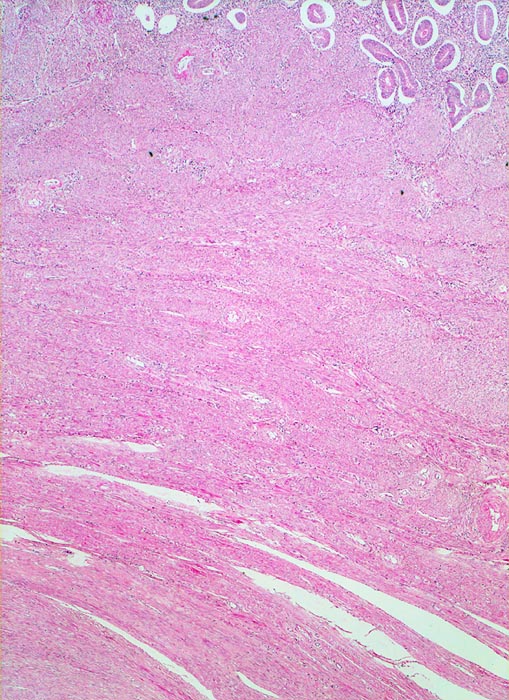

Oben im Bild ist das Stratum basale des Endometriums erkennbar. Die endometranen Drüsen sind von einem artefiziellen Spaltraum umgeben. Daran angrenzend das Myometrium. Im Myometrium ist ein scharf begrenzter unbekapselter glattmuskulärer Tumor erkennbar.

Vergrösserter 258g schwerer Uterus mit multiplen weissen, derben scharf begrenzten, teils intramuralen und teils submukös gelegenen Knoten.

Die Drüsen des Stratum basale zeigen während des ganzen Zyklus geringe Proliferationszeichen. Eine Zyklustagbestimmung ist hier deshalb nicht möglich.